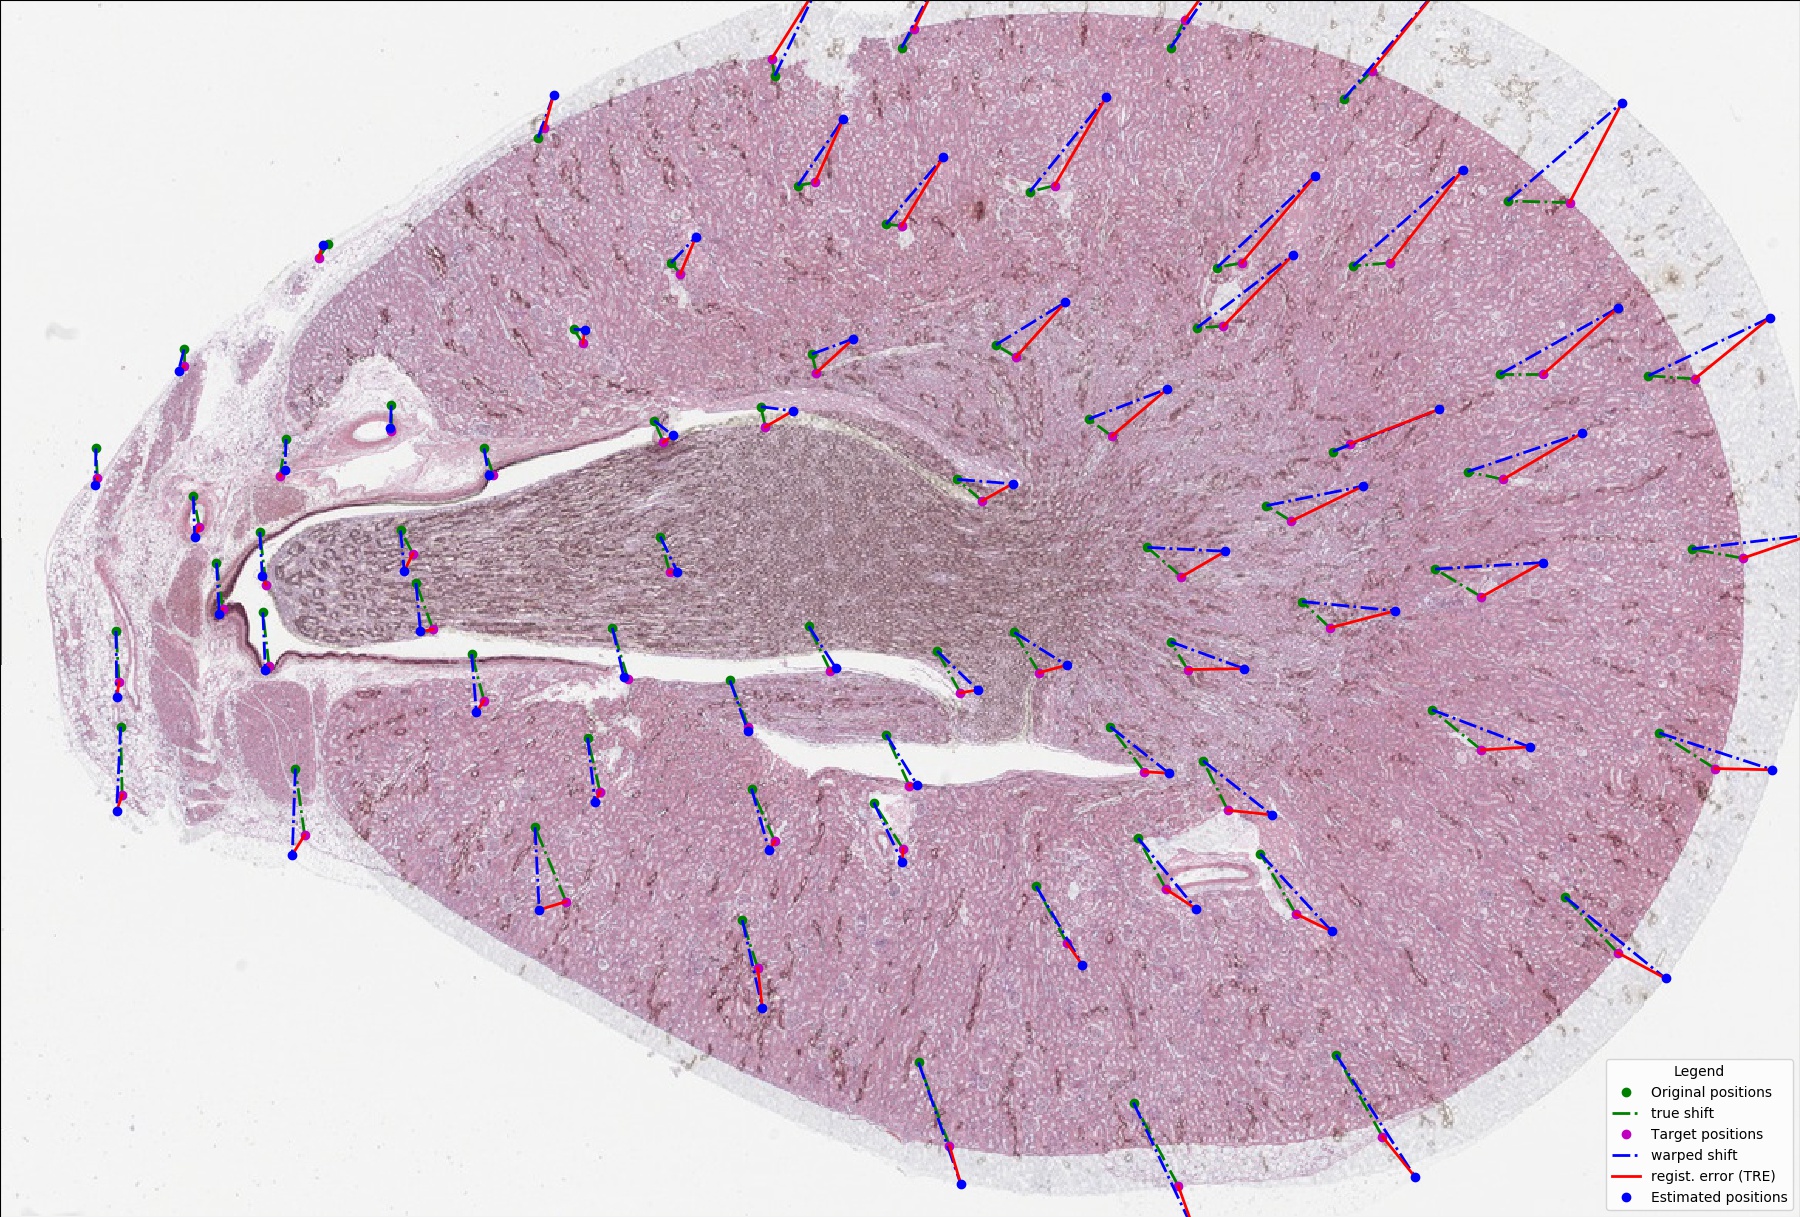

BIRL stands for "Benchmark on Image Registration methods with Landmark validation". BIRL is a cross-platform framework for comparison of image registration methods with landmark validation (registration precision is measured by user landmarks). The project contains a set of sample images with related landmark annotations and experimental evaluation of state-of-the-art image registration methods.

• integrated evaluation of registration performances using Target Registration Error (TRE)

• integrated visualization of performed registration